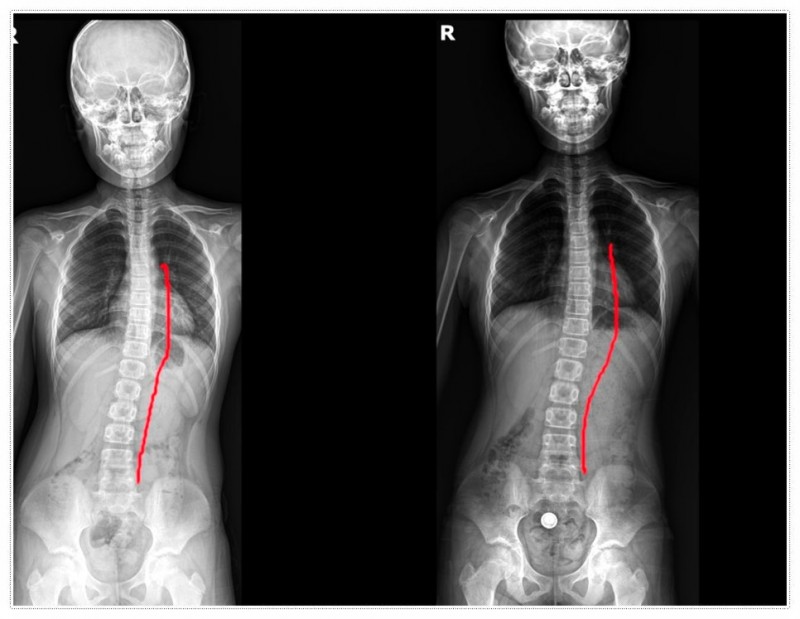

성장기 척추측만증은 조용히 시작해 어느 순간 눈에 띄게 드러나는 과정을 거치게 되는데요.

우리가 흔히 떠올리는 척추측만증은 단순히 옆으로 휘는 문제만을 의미하지 않습니다.

척추가 휘어지는 과정에서 골반, 어깨, 목까지 연쇄적으로 영향을 받을 수 있다는 점도 함께 고려해야 하는데요.

특히 성장판이 열려 있는 시기에는 척추측만증의 진행 속도가 빨라질 수 있어 더욱 주의가 필요합니다.